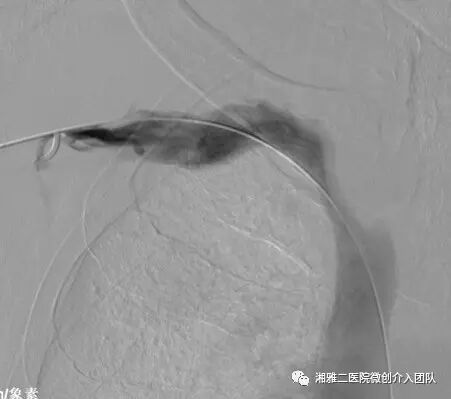

造影所见,可见无名静脉闭塞并侧枝形成

以上为再通过程